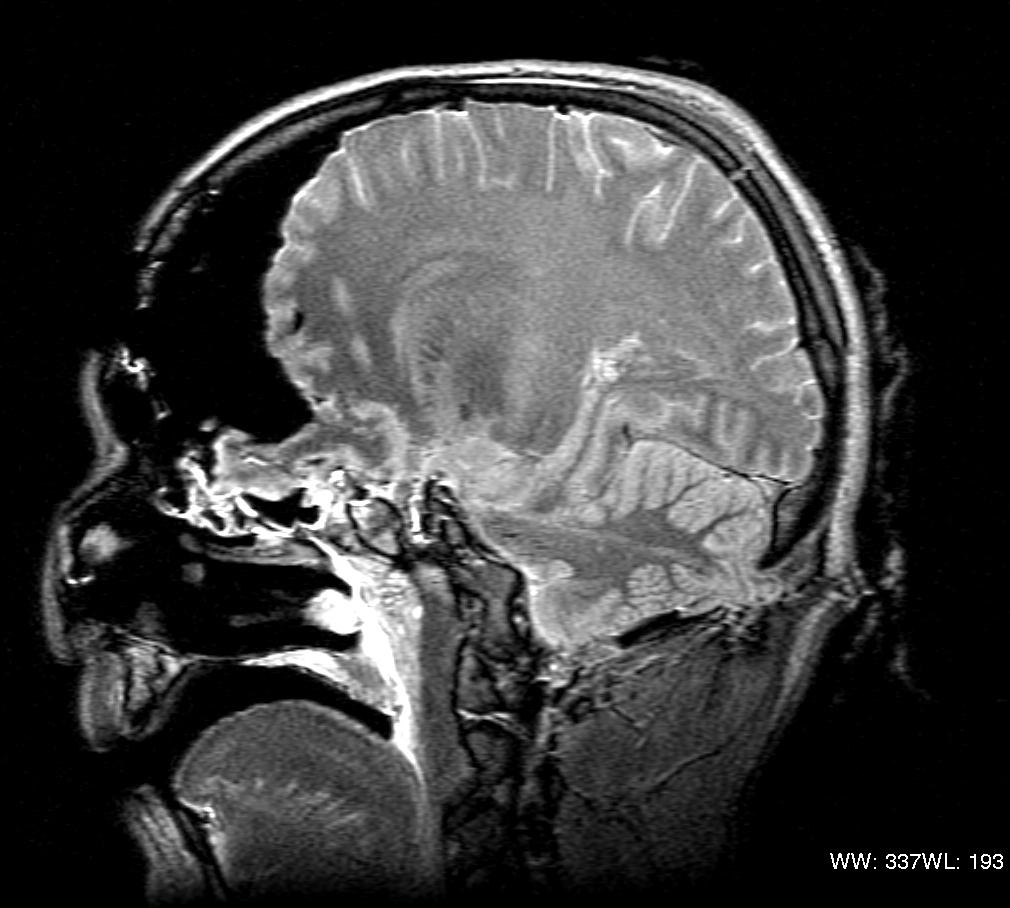

Suicidal Gunshot Wounds to the Head: A Retrospective Review… : The …

X-ray Showing A Gunshot Wound To The Head Digital Art by Callista …

GUNSHOT WOUND TO HEAD | buyxraysonline

Intra-Aortic Missile After Gunshot Wound to Chest: An Interesting Case …